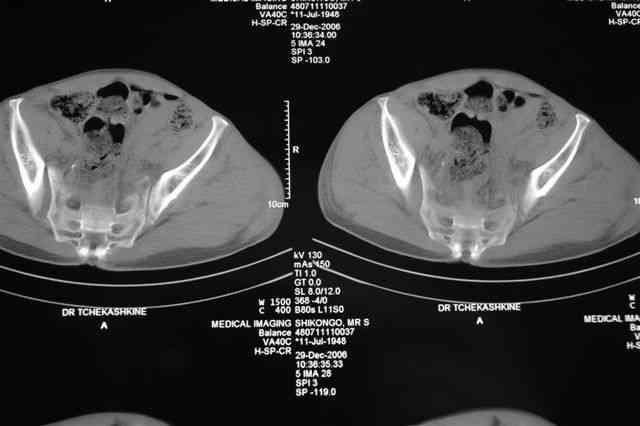

По-поводу фиксации таза спонгиозными винтами. Данный способ все-таки показан для фиксации повреждения крестцово-подвздошного сочленения или переломов крестца. Мне кажется, что в данной случае ситуация иная - имеется перелом "основания" крыла подвздошной кости (в который вовлечена и поверхность, составляющая крестцово-подвздошное сочленение). Не уверен, что фиксация данного повреждения (и заднего полукольца) винтами будет стабильной, так как именно на уровне 1-2 крестцовых позвонков (где обычно вводят винты) линия перелома уходит в латеральном направлении от крестцово-подвздошного сочленения.

PI>По-поводу фиксации таза спонгиозными винтами. Данный способ все-таки показан

для фиксации повреждения крестцово-подвздошного сочленения или переломов крестца. Мне кажется, что в данной случае ситуация иная - имеется перелом

"основания" крыла подвздошной кости (в который вовлечена и поверхность, составляющая крестцово-подвздошное сочленение). Не уверен, что фиксация данного повреждения (и заднего полукольца) винтами будет стабильной, так как

именно на уровне 1-2 крестцовых позвонков (где обычно вводят винты) линия перелома уходит в

латеральном направлении от крестцово-подвздошного сочленения.

Я просмотрел томограммы и у меня создалось впечатление, что винтам есть за что *зацепиться*. В сочетании с 5 мм Шанц винтами, проведенными через нижне-переднюю ость спереди назад через КП сочленения -стабильность тазового кольца должна восстановиться. - Это , конечно, при условии , что закрытая рнепозиция будет успешной.

PI>По-поводу репозиции костей таза. Производить репозицию костей все-таки необходимо. Пока я не встретил информации, сколько времени прошло с момента травмы, но одномоментно низвести правую половину таза может быть тяжело, учитывая и наличие перелома бедренной кости (что затруднит тракцию за нижние конечности).

Травма произошла 22 или 23 декабря, ко мне больной попал 26 декабря, 3 января -остеосинтез перелома бедра и внутр.лодыжки.

после КТ отказался от этой идеи - двусторонний перелом крестца в зоне 1 - алярная часть, при попытке низведения правого гемипелвиса теоретически есть вероятность смещения

фрагмента крестца слева.